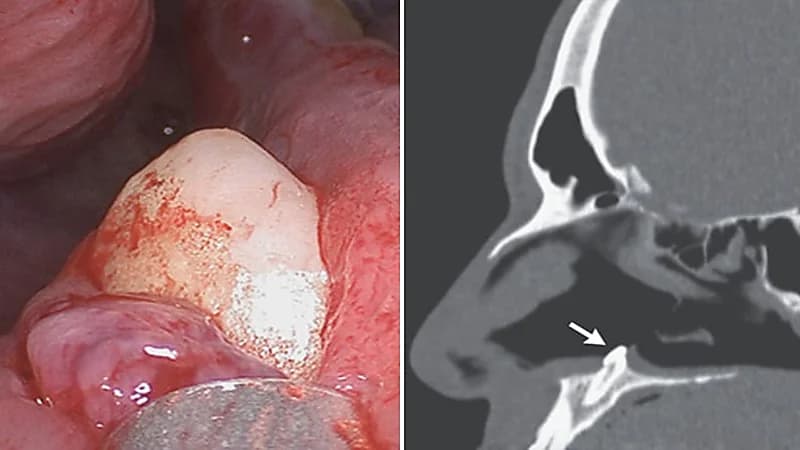

اكتشف جراحون وجود سنًا يبلغ طوله 15 ملم ينمو داخل فتحة أنف رجل أمريكي بعد أن تسبب هذا الأمر بصعوبة كبيرة له في التنفس.

وعاني الرجل من صعوبات في التنفس لسنوات عدة ليقرر الخضوع للفحص الطبي ويكتشف أنه يعاني من انحراف في الحاجز الأنف عندما يتم دفع الحاجز بين الممرات الأنفية إلى الجانب بالإضافة إلى نمو يشبه العظم في الأنف.

وأجرى الجراحون منظارًا واكتشفوا وجود كتلة بيضاء تظهر من خلال أرضية فتحة الأنف اليمنى ليكتشفوا وجود سن منتبذ يبلغ طوله 15 ملم، والذي يُعرّف بأنه يحتوي على ضرس في مكان غير طبيعي.

وتمكن الأطباء من إزالة الكتلة للمريض عن طريق جراحة داخل الأنف دون أي مضاعفات ما بعد الجراحة.